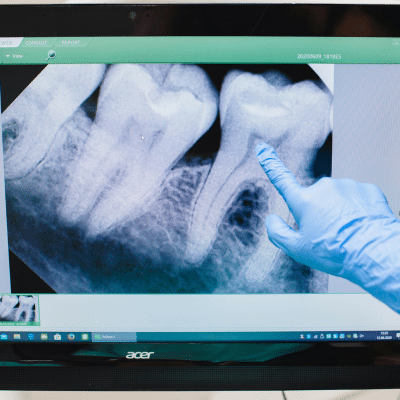

Stage 3: Dentin Decay

The third of the stages of tooth decay occurs when the cavity extends into the dentin, the softer layer beneath the enamel. Because dentin contains nerve endings, this stage often comes with noticeable discomfort.

Stage 4: Pulp Involvement

By the time decay reaches the pulp, you’ve entered one of the more serious stages of tooth decay. The pulp contains the tooth’s nerves and blood vessels, making this stage painful and potentially dangerous if left untreated.